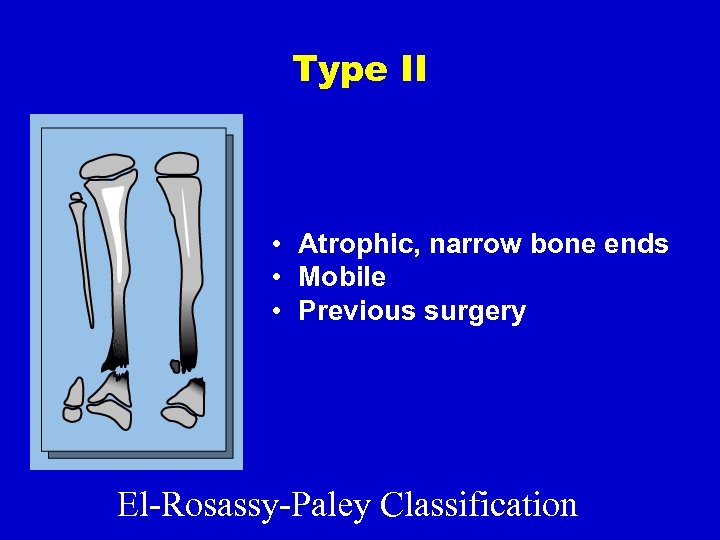

Type II • Atrophic, narrow bone ends • Mobile • Previous surgery El-Rosassy-Paley Classification